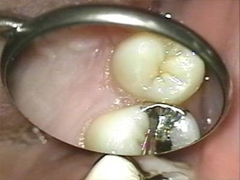

削らない虫歯治療

このくらいの虫歯であれば,無麻酔で治療を行えます。

痛みも音もないので、お子様や歯医者嫌いの方にとてもいい方法です。